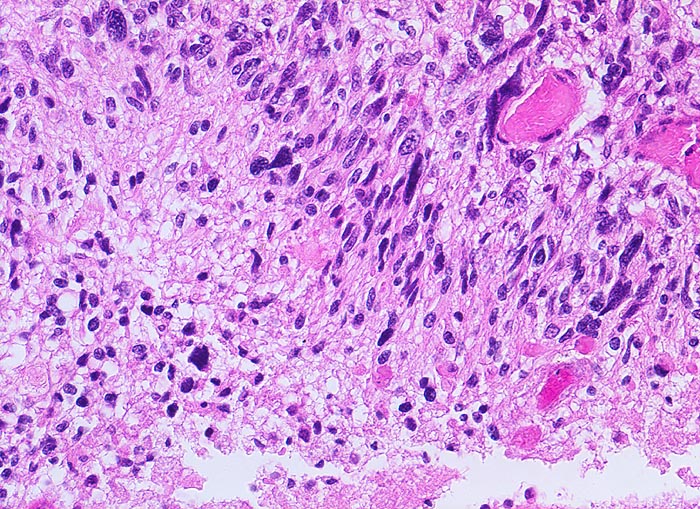

PathoPic ID 5200 - Glioblastoma multiforme (WHO IV)

Glioblastoma multiforme (WHO IV)

maligner Tumor

Hirn temporal

Nervensystem

Parallele Ausrichtung der Tumorzellen zueinander und senkrecht zur Tumornekrose links unten im Bild.

Seit zwei Monaten zunehmende Persönlichkeitsveränderungen, Kopfschmerzen und progrediente fokal neurologische Zeichen.

Histologie

200